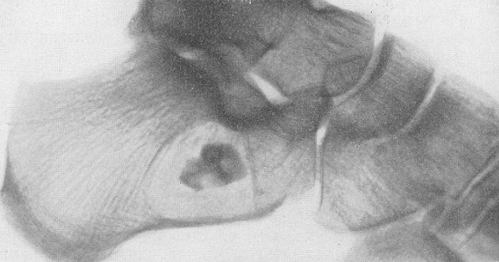

При наиболее фиксируемой в медицинской практике в первичной хронической форме патологический процесс характеризуется медленным течением. В пяточной зоне происходит язвенное повреждение покровных тканей (кожи), которое с течением времени увеличивает свои размеры и глубину. В этом случае язвенному участку свойственно следующее: в самом дне оголяется пяточная кость, ее можно легко визуализировать. По причине продолжительного течения эта кость начинает подвергаться процессу деструкции, в результате чего через отверстие высвобождаются части костной ткани (секвестры). Последние легко определяются и на рентгенологической пленке.

При возникновении описанных проявлений следует обратиться за консультацией к специалиста: травматологу либо хирургу. Диагностические мероприятия складываются из традиционной компьютерной томографии и рентгенографического исследования пяточной области. Как дополнительные диагностические мероприятия назначаются лабораторные исследования крови и мочи: общий и биохимический анализ.